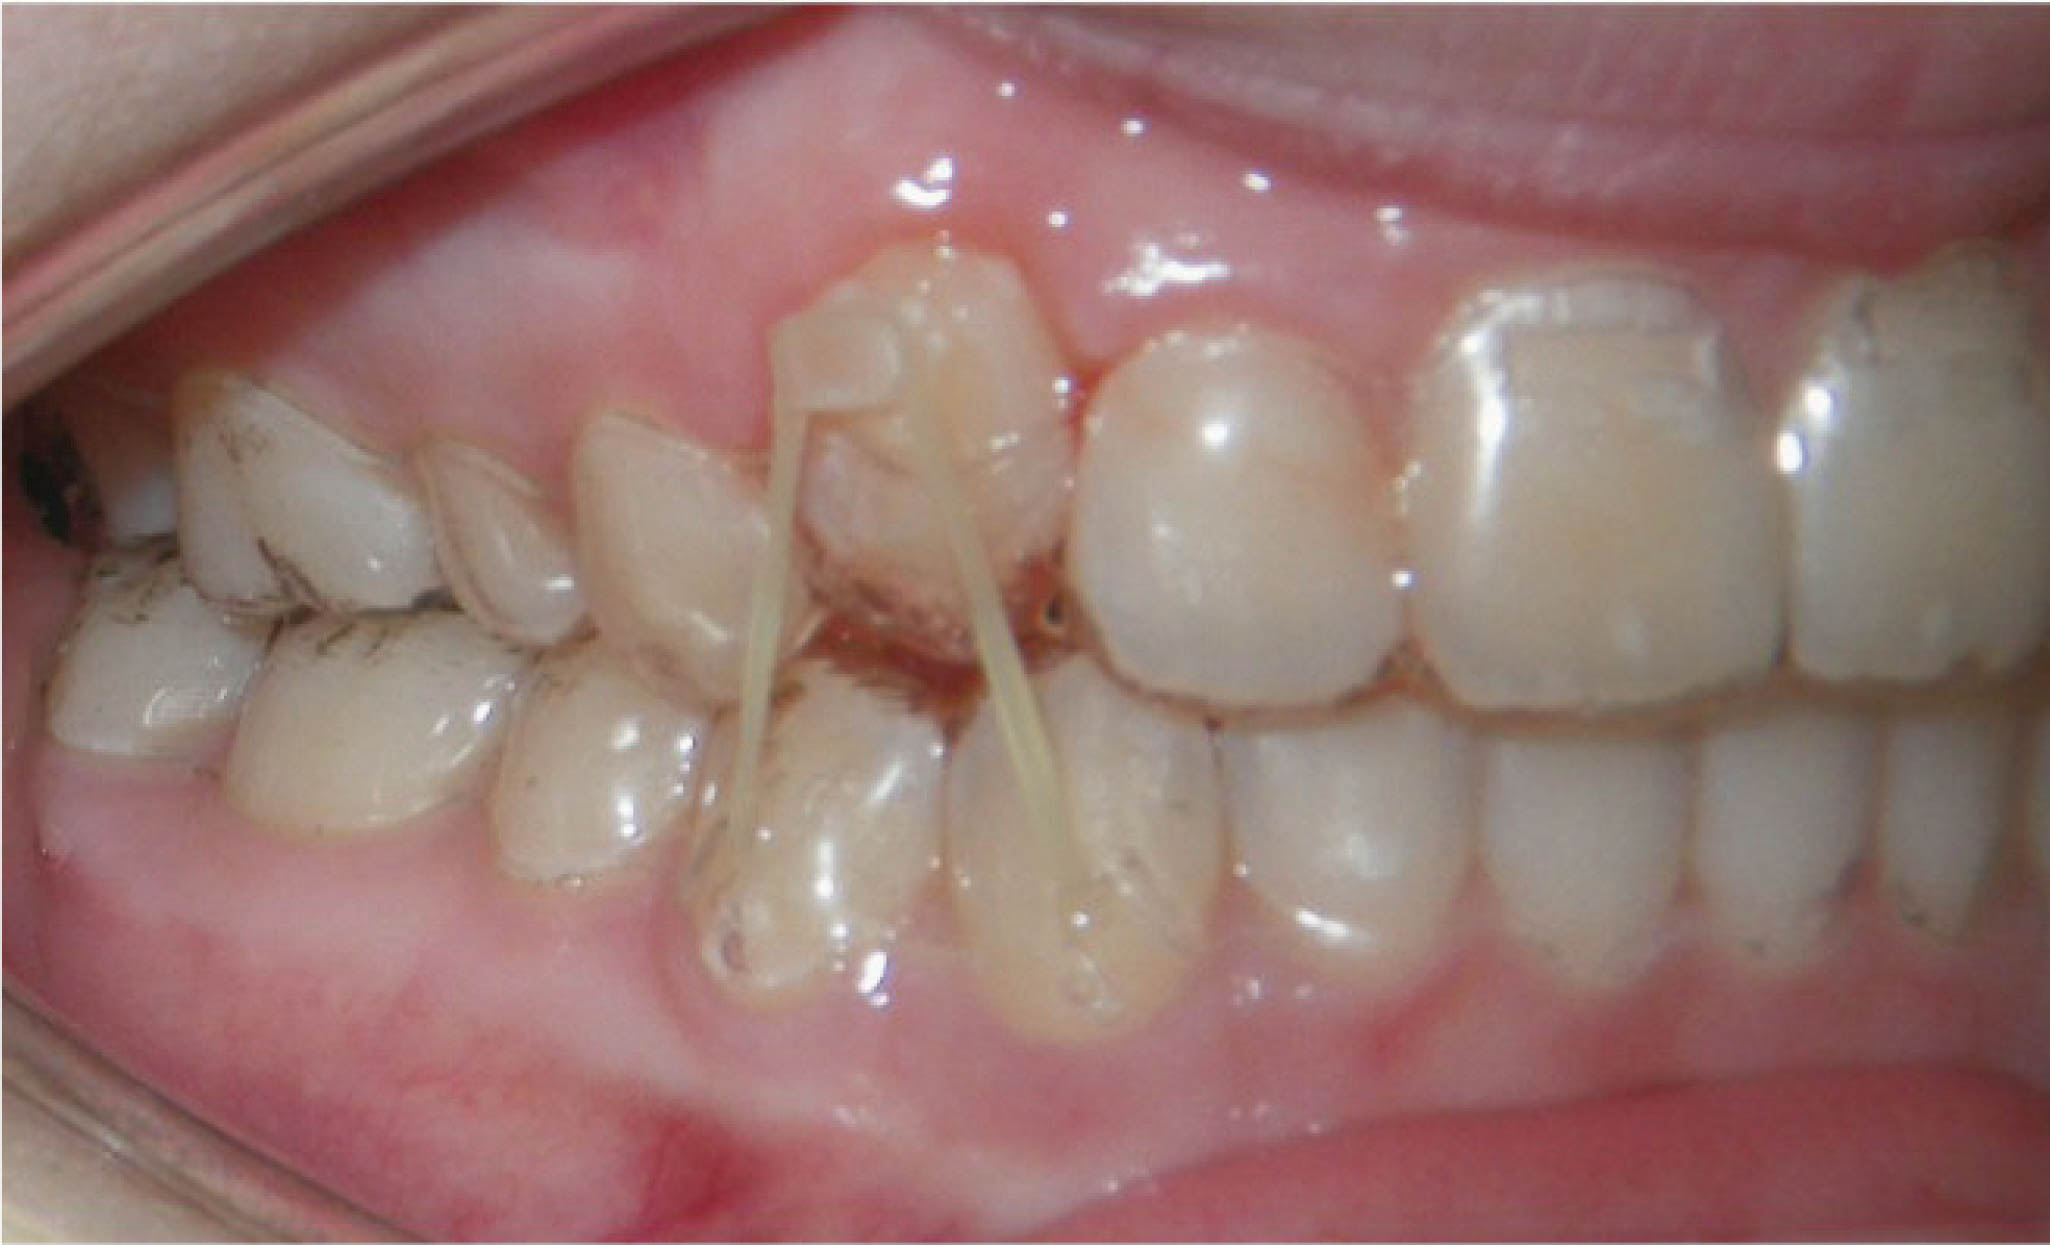

وقتی بی هیچ دلیلی دندان انسیزور بالا اکسترود نمیشود، از الاستیک استفاده میکنیم. در سمت لبیال سمت لثه یک قسمتی از الاینر را می بریم و یک باتن میگذاریم. در سمت لینگوپالاتال الاینر همین دندان هم یک برش مثلثی میدهیم تا حکم یک هوک را پیدا کند. بعد کش 16/3 به بیمار میدهیم تا از باتن به هوک سمت پالاتال بندازد به نحوی که از سطح انسیزال رد بشود. این الاستیک نیرویی روی دندان میگذارد که منجر به اکسترود شدن آن به درون فضای الاینر میشود. این الاستیکها (شکلهای 169-6 الی 171-6) در درمان اکستروژن بسیار موثر هستند

شکل 169-6

شکل 170-6

شکل 171-6